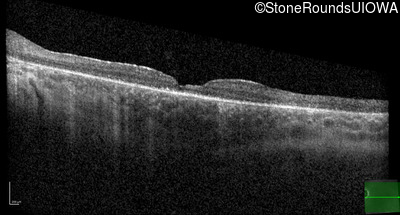

Optical Coherence Tomography - Right - 20/50

Exemplar / OCT Stack

OCT Stack